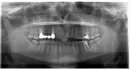

Неделю назад стала беспокоить боль в 14-м зубе при надкусывании и боль в верхней части над зубом при надавливании пальцем. Сразу обратилась в клинику, где проходила лечение и устанавливала конструкцию. Врач сделала рентген. На рентгене ничего не увидела. Сделала чистку ультразвуком, положила лекарство, назначила полоскание и Метрогил Дента, также Нурофен 3 дня. Сказала воспаление в кармане возможно. Боль не прошла, а только усилилась. Через 3 дня сделала снимок и мне кажется, что все-таки имеется воспаление на верхушке корня, а также, на мой взгляд, не совсем корректное пломбирование канала между запломбированным корнем и культевой вкладкой маленькое пространство.

По данному рентгеновскому снимку за верхушкой корня 16-го зуба есть воспалительный процесс (зуб следует удалить).

13-й зуб необходим прицельный рентгеновский снимок, чтобы оценить периапикальную область. Скорее всего его, придется тоже удалить, так как мало здоровых твердых тканей над десной для последующего восстановления коронкой. Есть риск трещины корня при извлечении вкладки.

Чтобы составить план лечения для имплантации отсутствующих зубов, необходима диагностика компьютерная томография, по которой можно оценить уровень костной ткани. Возможно понадобится проведение костной пластики.